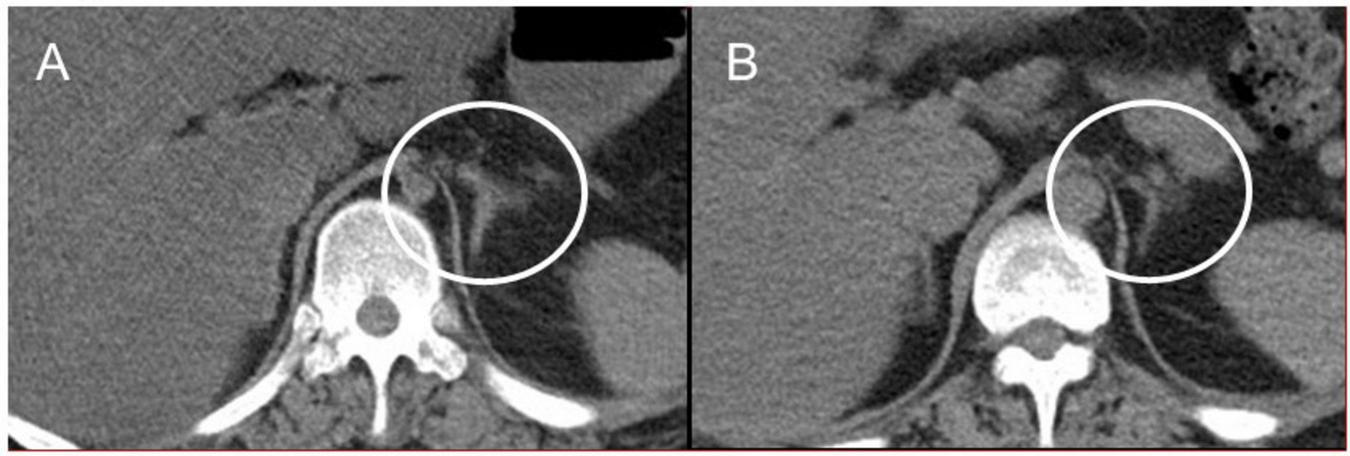

Autopsy imaging using computed tomography (CT) showed enlargement and high density of the left adrenal glands compared to its normal appearance on images taken 5 months prior (Figure 1). Postmortem anatomical examinations revealed the presence of an accumulation of inflammatory cells in the renal pelvis and renal medulla. Despite the absence of bacteriological evidence, the pathology report indicated the presence of pyelonephritis (Figure 2). They also revealed an adrenal hemorrhage and necrosis (Figure 3), with the left adrenal gland showing more severe hemorrhage and necrosis compared to the right. Numerous erythrophagocytic macrophages were observed in the bone marrow (Figure 4), spleen (Figure 5), and liver. Acute splenitis with neutrophil infiltration, indicative of sepsis, was also observed in the spleen (Figure 5). The renal glomerular fibrin thrombus, confirming disseminated intravascular coagulopathy (DIC), was identified (Figure 6). Hemorrhagic diathesis secondary to DIC was evident with intra-alveolar, subpleural, subperitoneal, and ileal mucosal bleeding. The likely source of the E. coli leading to sepsis was identified as pyelonephritis. The autopsy concluded that the cause of death was acute adrenal insufficiency due to BAH and hemophagocytosis associated with sepsis caused by E. coli.

FIGURE 1

Abdominal CT images. (A) Postmortem CT imaging reveals hyperdensity in the left adrenal gland (indicated by a circle), suggestive of adrenal hemorrhage. (B) A CT scan performed 5 months prior to admission shows no abnormalities in the left adrenal gland (indicated by a circle). CT, computed tomography.

Suspecting acute adrenal insufficiency, including classical Waterhouse-Friderichsen syndrome, but constrained by the rapid clinical progression, we could not perform some tests including endocrinological tests. Autopsy findings revealed an enlarged left adrenal gland and bilateral hemorrhage with necrosis of the adrenal cortices. Over the years, there have been reports of BAH related to multiple etiologies, including various systemic bacterial and viral infections (9, 10), with Neisseria meningitidis as a notable causative agent of BAH. However, cases of BAH resulting from E. coli infection are rare (11–13). Although E. coli is a common microorganism, many internists may overlook the complications associated with BAH. BAH, leading to adrenal insufficiency (15, 16), is often predisposed by DIC (17, 18). While antemortem diagnosis of BAH is challenging, serial CT imaging of the abdomen is valuable (15, 16), as confirmed by our autopsy imaging.